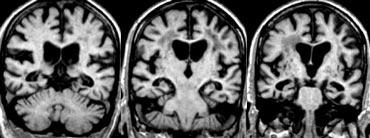

Hình ảnh mặt phẳng coronal cho thấy hồi hải mã, cấu trúc chính liên quan đến nhiều thể sa sút trí tuệ.

Điểm MTA cần được đánh giá trên chuỗi xung T1W mặt phẳng coronal tại một vị trí lát cắt nhất quán.

Chọn lát cắt qua thân hồi hải mã, ở mức cầu não trước.

Điểm số được tính dựa trên đánh giá trực quan chiều rộng của khe mạch mạc, chiều rộng của sừng thái dương và chiều cao của cấu trúc hồi hải mã.

- Điểm 0: Không có teo não

- Điểm 1: Chỉ giãn rộng khe mạch mạc

- Điểm 2: Kèm theo giãn rộng sừng thái dương của não thất bên

- Điểm 3: Mất thể tích hồi hải mã mức độ vừa (giảm chiều cao)

- Điểm 4: Mất thể tích hồi hải mã mức độ nặng

< 75 tuổi: Điểm từ 2 trở lên là bất thường.

> 75 tuổi: Điểm từ 3 trở lên là bất thường.

Tại đây bạn có thể cuộn qua các hình ảnh minh họa điểm MTA từ 0 đến 4.